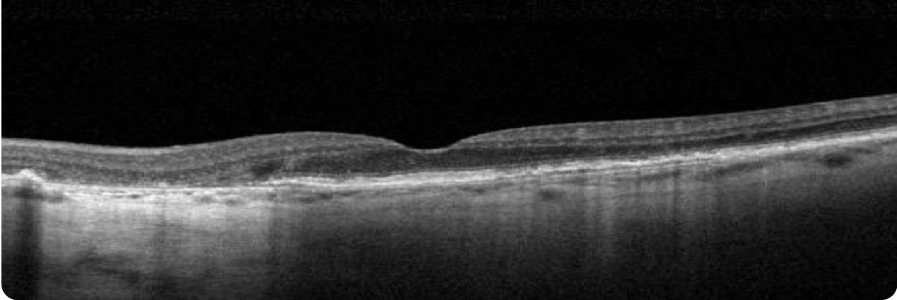

BASELINE VISIT

- BCVA: 6/7.5

- Visual function: Patient requires assistance from a caregiver on some activities (eg, cooking, driving), since pericentral vision is lost due to GA

OCT

4 YEARS AFTER BASELINE VISIT

- BCVA: 6/15

- Visual function: Although patient maintains relatively good BCVA, she has poor visual quality. Patient relies heavily on caregiver for assistance with many activities of daily living

Although there is significant atrophy, the fovea remains relatively spared from GA.

Images courtesy of Mohammad Rafieetary, OD, Charles Retina Institute.